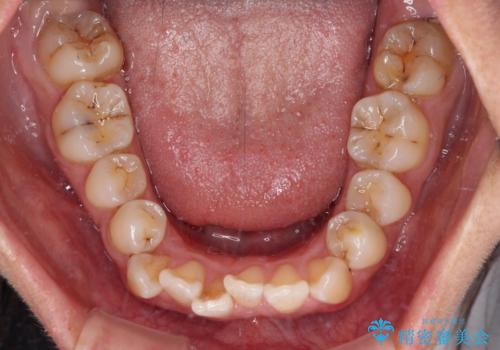

- 前歯のデコボコを治したいとのことで来院された患者様です。

上下顎ともに歯列全体の後方移動とIPR(歯と歯の間を削る)によってデコボコが解消するように設計し、インビザラインにより治療を行うこととしました。

下顎前歯は後戻りを起こしやすいため、舌側を細いワイヤーで固定し、マウスピース型リテーナーで保定を行うこととしました。